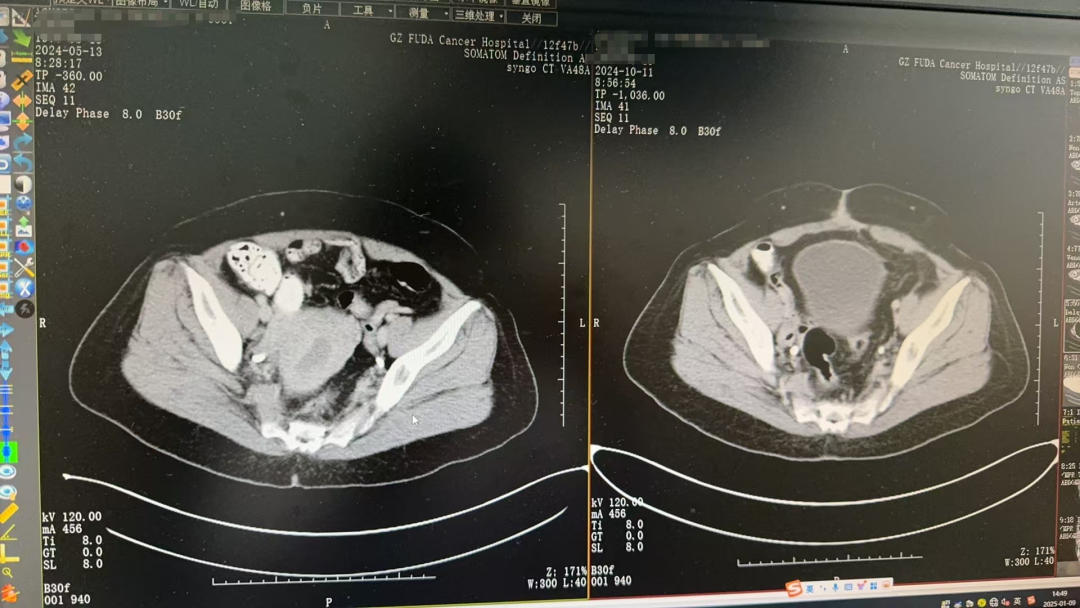

△左圖為治療前,右圖為手術(shù)后影像

“考慮腫瘤是早中期,首選治療以手術(shù)切除為主?!苯Y(jié)合Agustian入院后及既往檢查結(jié)果,臨床診斷為子宮內(nèi)膜癌2期。經(jīng)過(guò)多學(xué)科討論和評(píng)估后,Agustian接受了開(kāi)腹廣泛子宮切除術(shù)+雙側(cè)附件切除術(shù)+盆腔淋巴結(jié)清掃術(shù)。術(shù)后結(jié)合臨床和免疫組化結(jié)果顯示,病變符合子宮內(nèi)膜樣癌,腫瘤從頸管內(nèi)口至子宮體部,范圍約9×6×5cm,已侵及深肌層,侵犯深度約1.3cm。